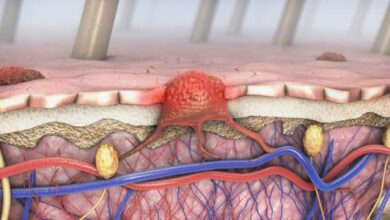

يتمثل ورم الرأس أو ورم الدماغ (Brain tumor) بنمو كتلة من الخلايا غير الطبيعية في الدماغ، ومع ازدياد حجم الورم قد يزداد الضغط داخل الجمجمة، سواءاً كان هذا الورم حميداً أو سرطانياً، وهذا ما قد يتسبّب بحدوث تلف في خلايا الدماغ، ويعرّض حياة المصاب للخطر.

وتجدر الإشارة إلى أنّه من الممكن تقسيم أورام الدماغ إلى نوعين رئيسيين، أمّا النوع الأول فهو الأورام الأولية (Primary tumors)؛ وهي الأورام التي بدأ نموها من الدماغ بحدّ ذاته، وقد تكون حميدة أو سرطانية، وأمّا النوع الثاني فهو الأورام الثانوية (Secondary tumors)؛ وهي الأورام التي بدأ نموها من جزء آخر في الجسم وانتشرت بعد ذلك ووصلت إلى الدماغ، ودائماً يكون هذا النوع من الأورام سرطانياً في طبيعته.[١]